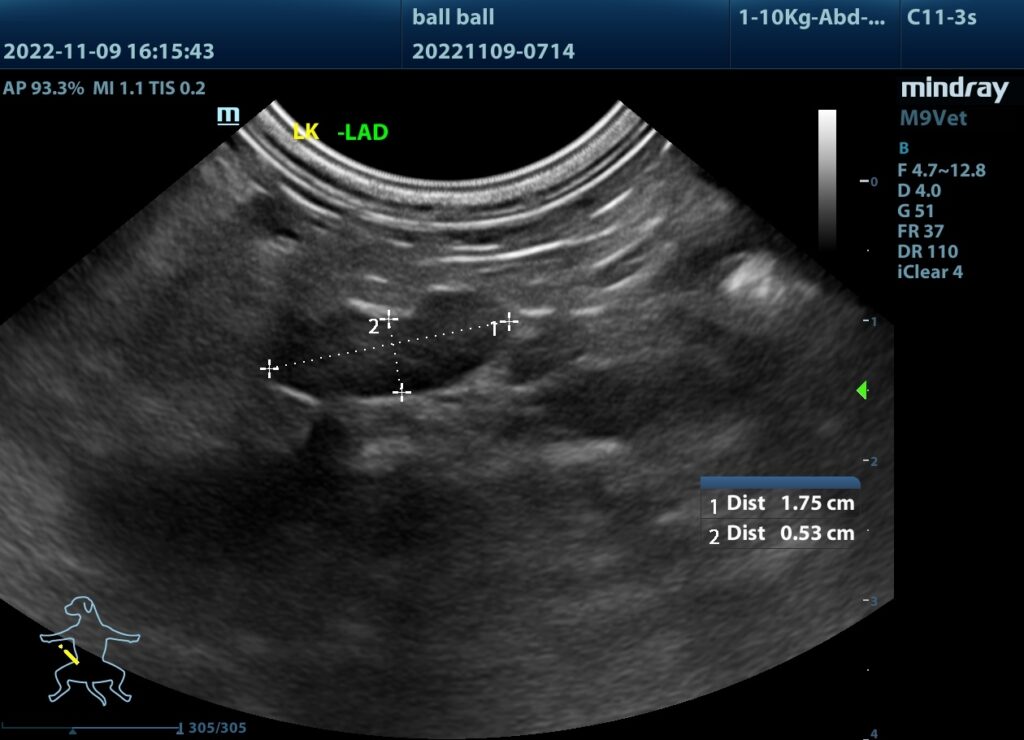

(2)超音波看見腫大的腎上腺。

腫大的腎上腺